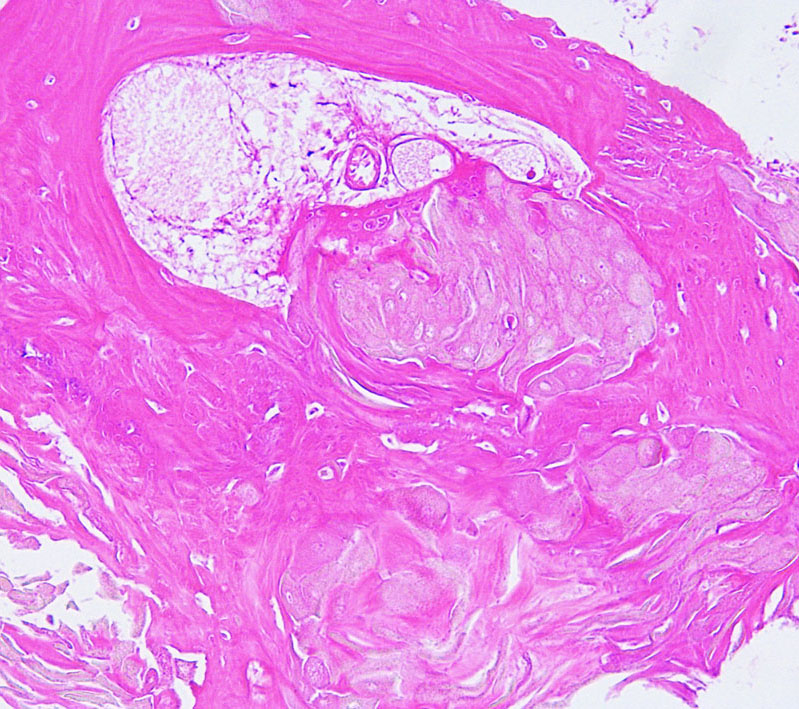

Craniopharyngioma with wet keratin structures (upper left) and calcification (upper right).

Adamantinomatous craniopharyngioma showing well-differenciated squamous epithelium including whorl of squamous cells. MIB-1 index of the dense basal layer was approximately 10%.